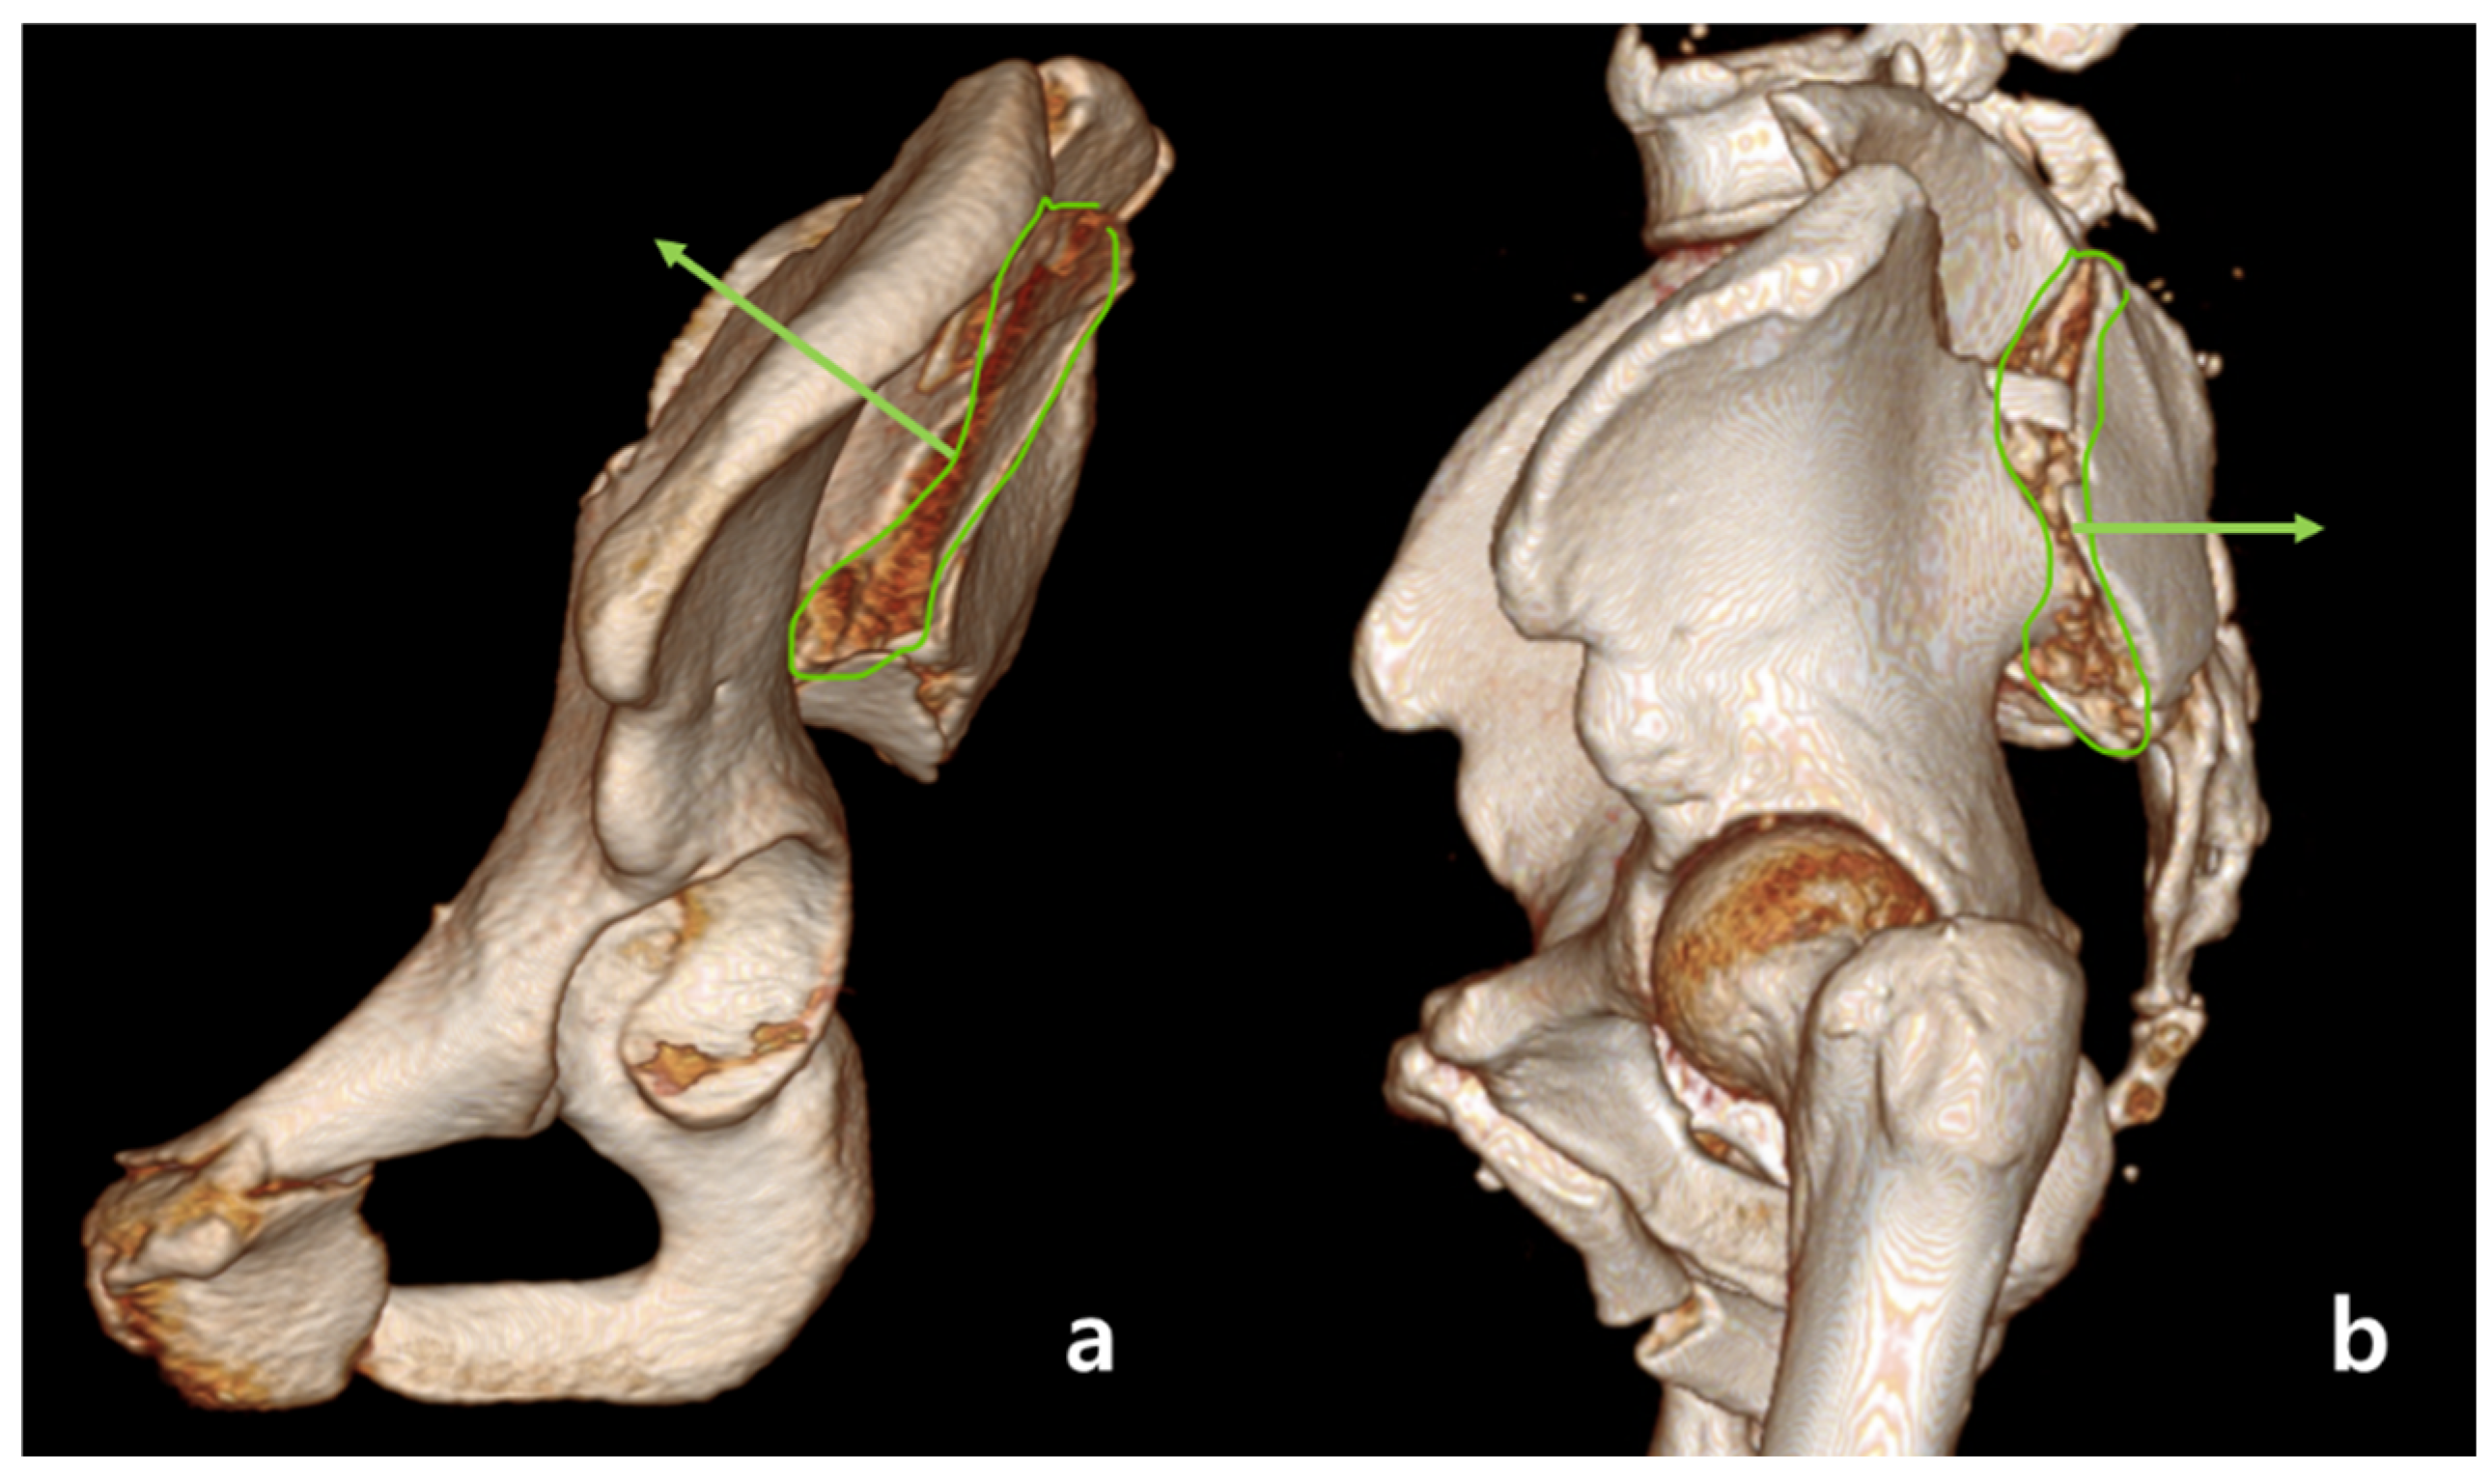

2.1. Classification of Fracture

2.2. Definition of Anterior Sacroiliac Fracture Dislocation